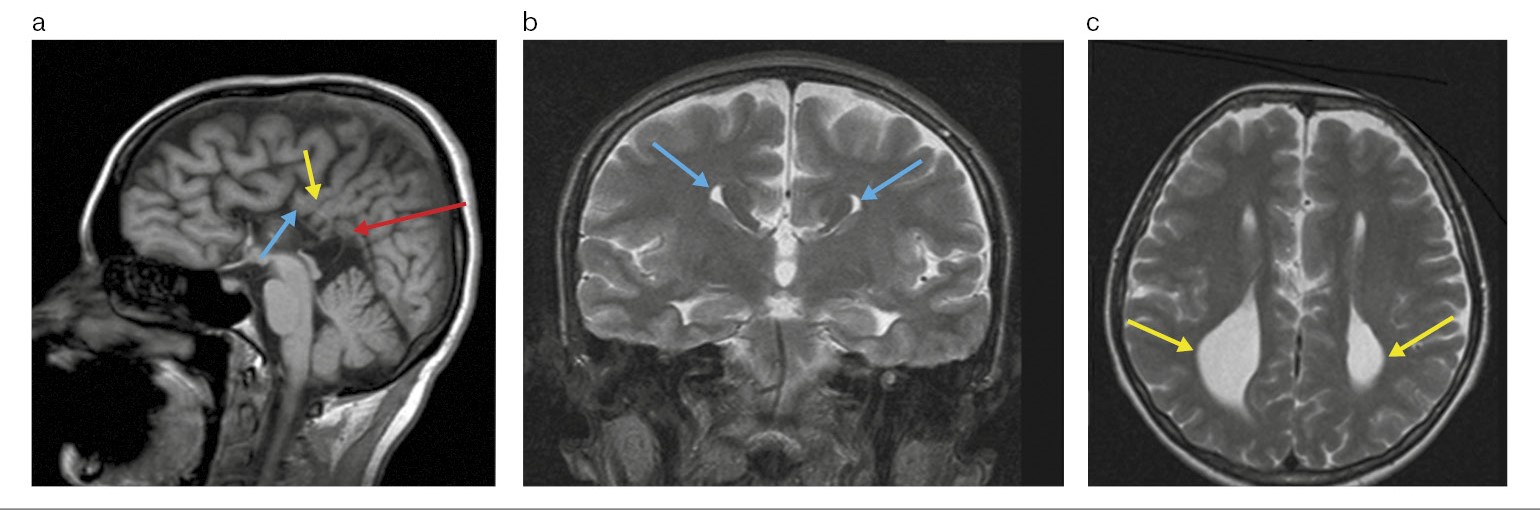

По данным МРТ ГМ срединные структуры не смещены. Очаговых и диффузных изменений вещества ГМ не выявлено.

В сагиттальной проекции выявлено отсутствие МТ. Прозрачная перегородка не определяется. На этом фоне боковые желудочки мозга симметричны, расширены преимущественно за счет задних рогов справа до 16 мм, слева – до 21 мм. Медиальные стенки боковых желудочков параллельны друг другу, III желудочек расширен до 13 мм, располагается между боковыми желудочками.

Длина передних рогов латеральных желудочков справа и слева составляет по 25 мм.

Имеется расширение крыши III желудочка. Межполушарная борозда спускается вниз до крыши III желудочка. Определяется аномальная поясная извилина.

Миндалины мозжечка расположены на уровне большого затылочного отверстия, не выступая за его пределы.

При внутривенном контрастировании отмечается венозная мальформация в левой лобной доле протяженностью <30 мм.

Заключение: МРТ-картина полной АМТ. Отсутствие прозрачной перегородки. Венозная мальформация в левой лобной доле (рис. 5).

Рис. 5. Больной П., 50 лет. МРТ ГМ: a – Т1-взвешенное последовательное изображение в сагиттальной плоскости: полное отсутствие МТ (белая стрелка); расширение крыши III желудочка (красная стрелка); аномальная поясная извилина (желтая стрелка); нижний сагиттальный синус (зеленая стрелка); b – Т2-взвешенное последовательное изображение в коронарной плоскости: симптом «шлем викинга» – поясная извилина вывернута в виде суженных и удлиненных лобных рогов (желтые стрелки); c – Т2-взвешенное последовательное изображение в аксиальной плоскости. Боковые желудочки мозга расширены за счет задних рогов: справа – 15 мм, слева – до 21 мм (голубые стрелки); III желудочек расширен до 13 мм – симптом «гоночного автомобиля» (розовые стрелки); d – Т1-взвешенное последовательное изображение в коронарной плоскости с контрастированием. Отмечена венозная аномалия развития лобной доли в виде мальформации (зеленая стрелка).

Консультирован неврологом. Признаков неврологического и когнитивного дефицита не установлено. Выполнена ЭЭГ. Изменений биоэлектрической активности не выявлено.

Окончательный диагноз «сочетанная полная АМТ с отсутствием прозрачной перегородки и венозной мальформацией в левой лобной доле».